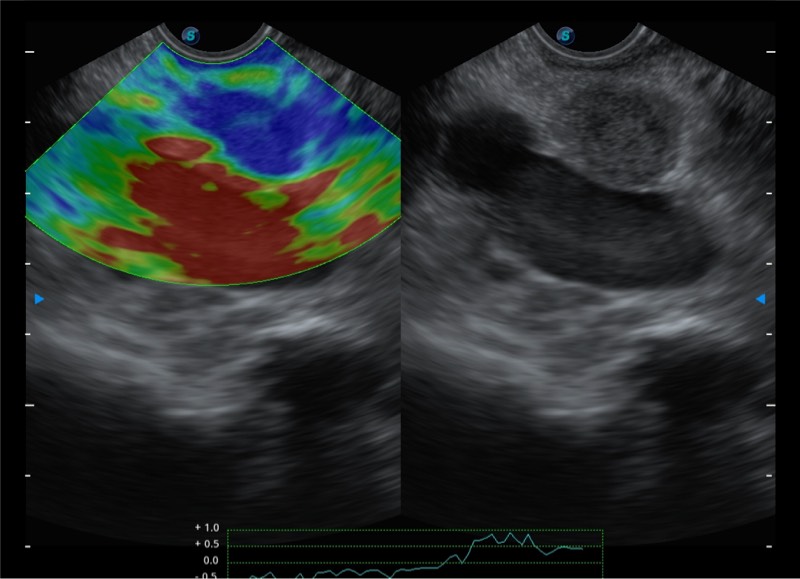

搭载百万级CMOS成像技术

及自主研发凸阵换能器,

可呈现优质的内镜和超声画面

基于二十年的超声技术积累,16877太阳集团提供了最新一代的独立超声主机,在提供高质量图像的同时满足多学科使用。具备常见多普勒技术并提供弹性成像、声学造影等高端影像技术。新一代传感器具有更强的抗干扰能力并减少图像伪影。

4-12MHZ宽频输出